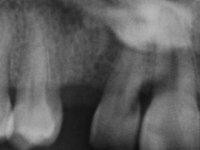

Female patient, 43 years old, non-smoker. Showed an edentulous space in the upper right canine area, resulting from tooth 1.3 impaction. The space had a mesio-distal diameter reduced to the normal size of the upper canine. This is consistent with the presence in the arch of the deciduous canine up to two years ago). Orthopantomography allows clearly view of tooth 1.3 impaction.The patient has a thick gingival phenotype and tolerable oral hygiene.